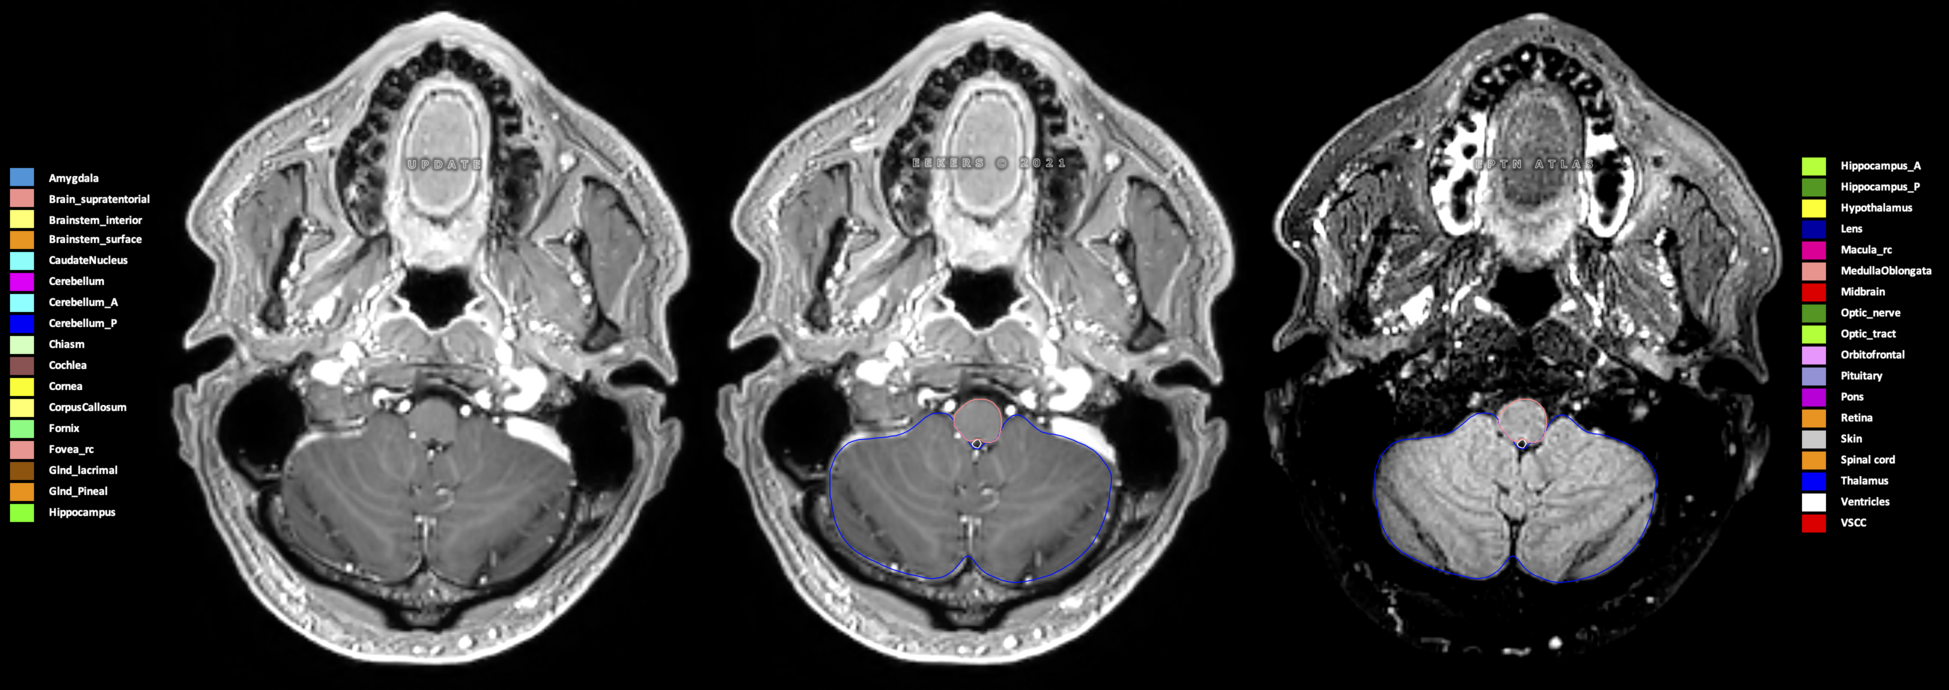

Eekers et al. have published an international neurological atlas for contouring of organs at risk in consensus with the European Particle Therapy Network (EPTN) in 2018 and an update in 2021. The purpose of this consensus atlas is to decrease inter- and intra-observer variability in delineating OARs relevant for neuro-oncology.

Included are all OARs known to be relevant for radiation-induced toxicity in neuro-oncology: brain, brainstem (midbrain, pons, medulla oblongata), chiasm, cerebellum (anterior & posterior), cochlea, cornea, hippocampus (anterior & posterior), hypothalamus, lens, lacrimal gland, optic nerve, pituitary, skin, and vestibular & semicircular canals. To further facilitate research on cognition, vision and radiological changes after irradiation of the brain, potential clinically-relevant OARs are included: amygdala, caudate nucleus, cerebellum (anterior & posterior), corpus callosum, fornix, macula, optic tract, orbitofrontal cortex, periventricular space (PVS), pineal gland, and thalamus.

Three-dimensional delineation of the 25 consensus OARs for neuro-oncology are shown on CT (WW/WL 120/40, 3000/600), 3T MR images, (T1Gd, T2FLAIR 1mm) and 7T MR (MP2RAGE 0.7 mm). All are presented in transversal, sagittal and coronal view.